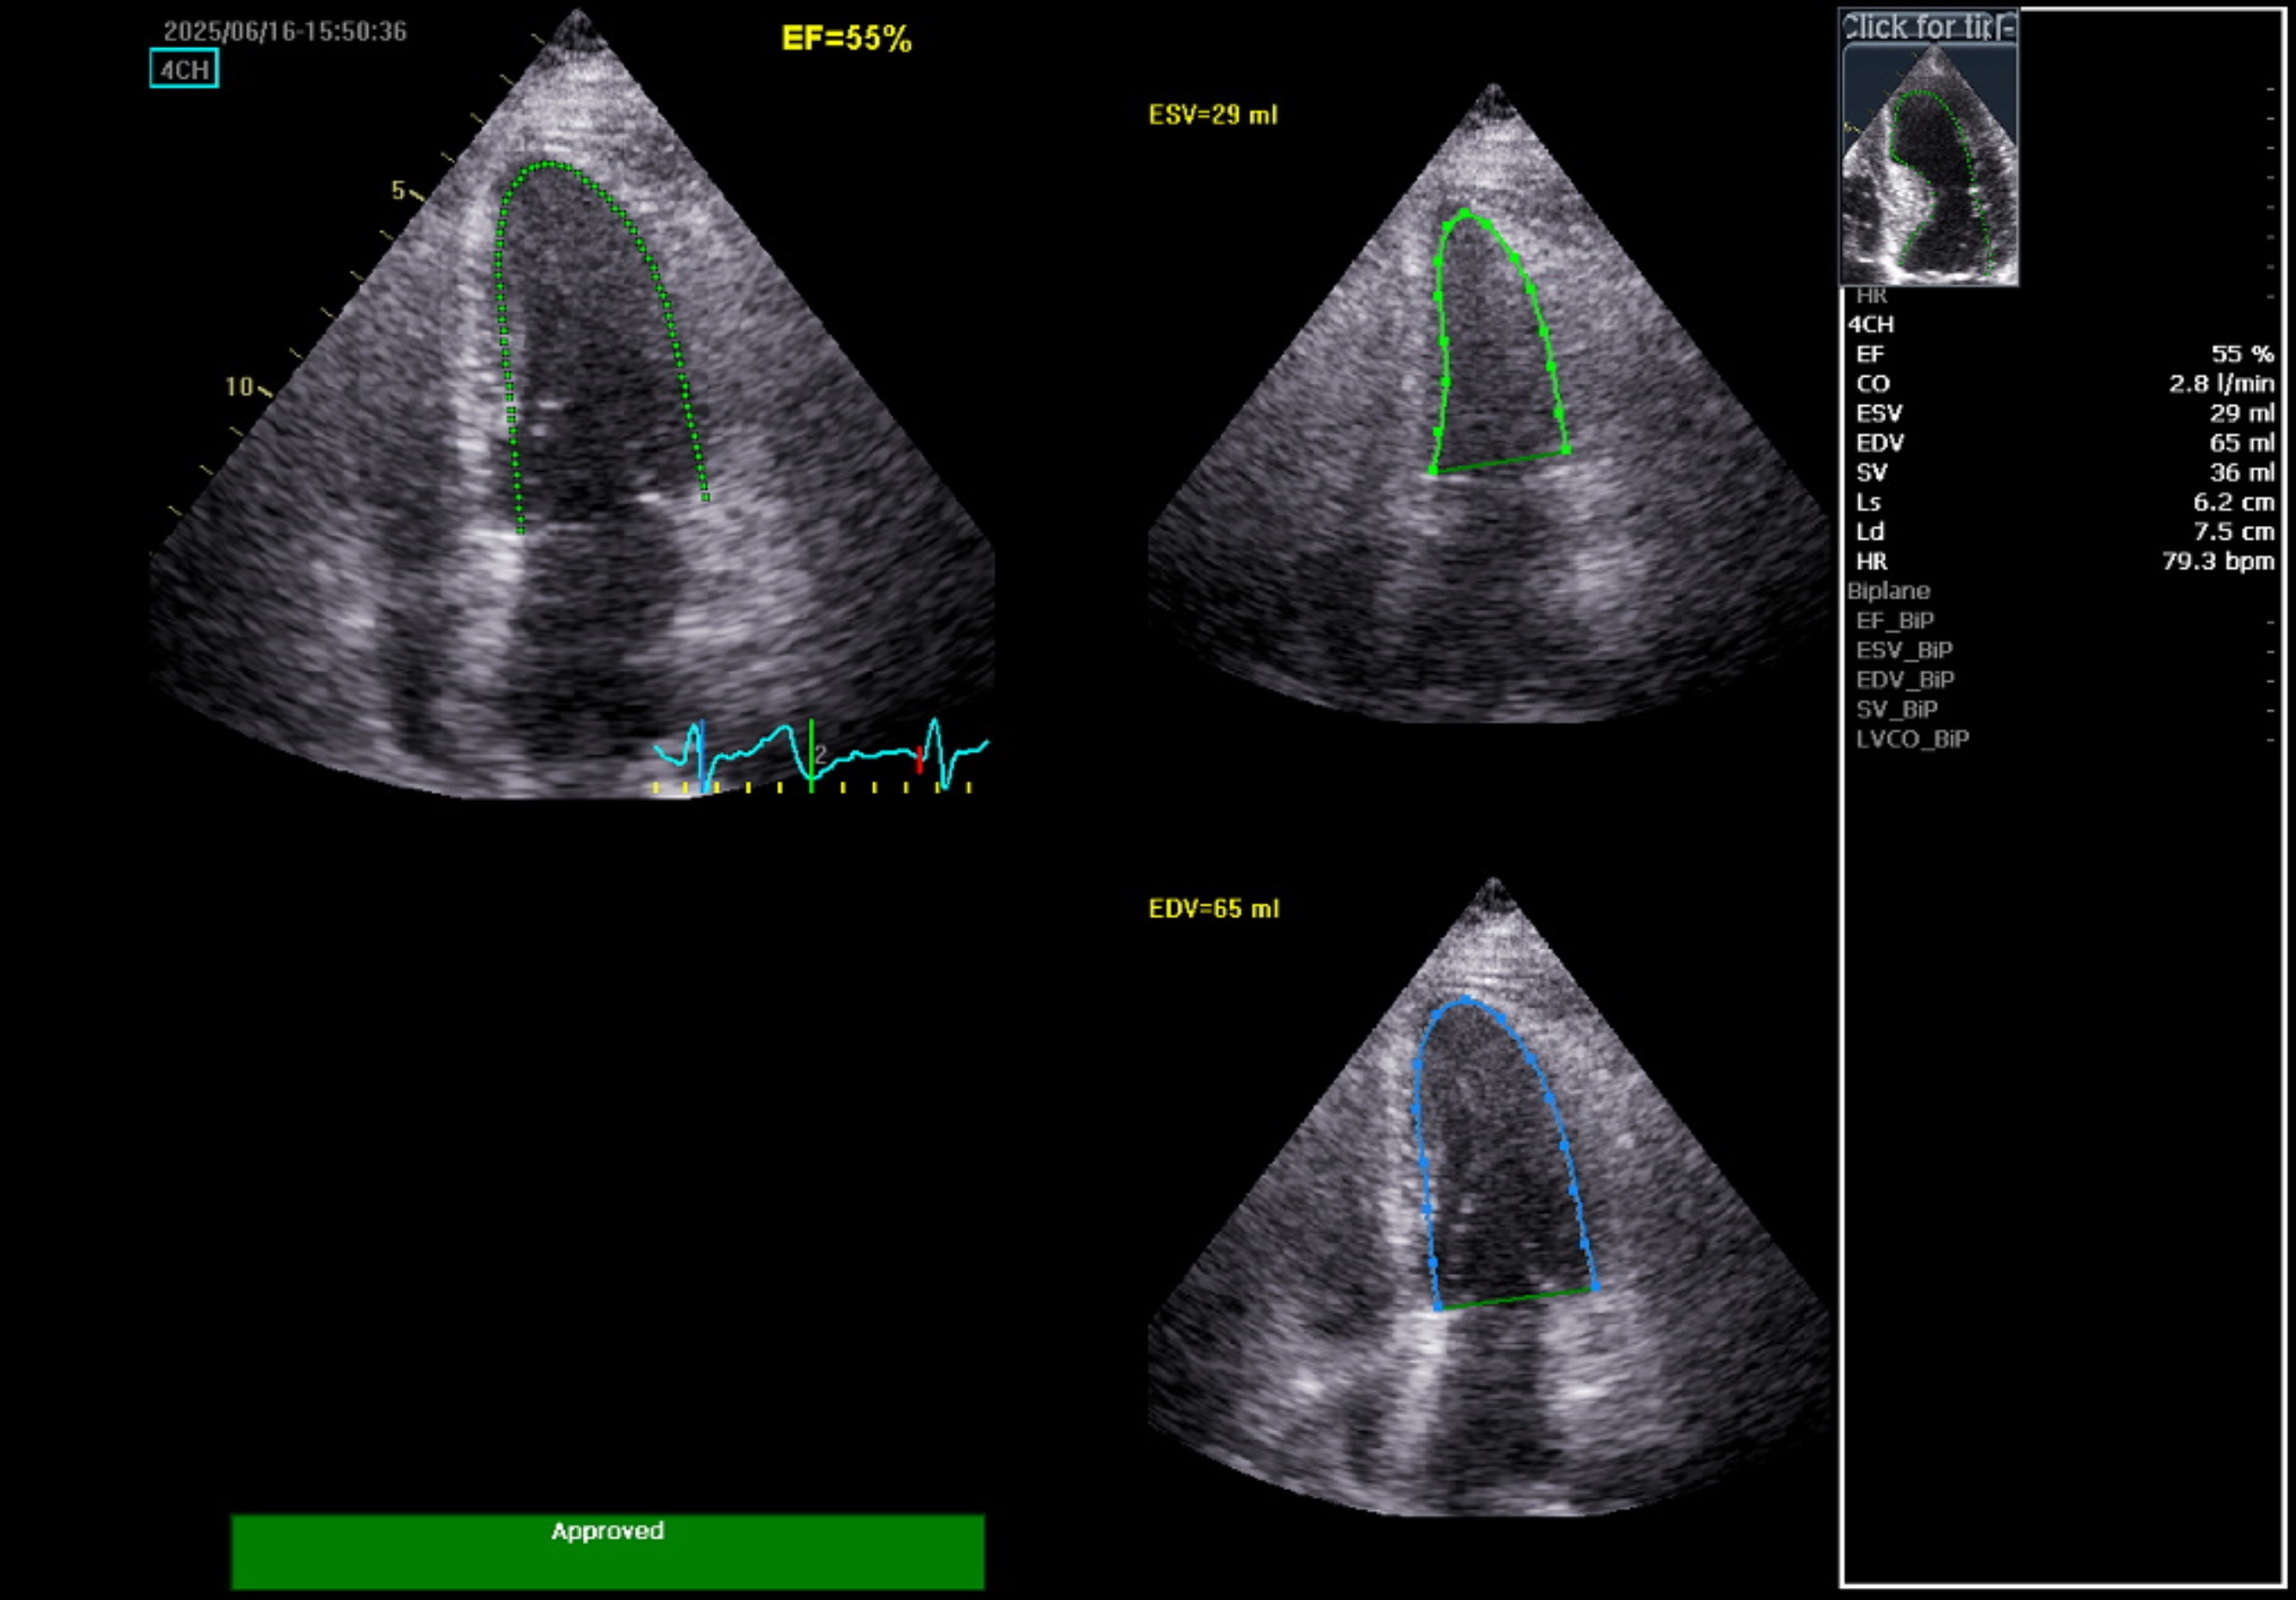

Relevant Test Results Prior to Catheterization

The initial electrocardiogram indicated sinus rhythm and normal axis without Left Ventricular Hypertrophy (LVH). No changes in the ST segment or T wave were noted. High-sensitivity troponin levels were serially elevated, suggesting Myocardial Infarction (MI). The echocardiography, however, showed no regional wall motion abnormality (RWMA) with preserved Left Ventricular systolic function (Ejection Fraction 55%). All cardiac valves were normal with no evidence of stenosis or regurgitation.